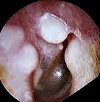

Удаление остеомы или экзостозов наружного слухового прохода

Удаление остеомы или экзостоз наружного слухового канала. Иссечение доброкачественных новообразований кости, как правило, располагается на передней и задней верхней стенке слухового прохода. Производится в стационарных условиях под местной анестезией или общей анестезией. Показанием к операции является уменьшение просвета слухового прохода, сопровождающееся выраженностью и шумом в ухе, нарушением слуха. При плоских экзостозах решение о вмешательстве принимается с осторожностью, поскольку операционная травма часто превышает ожидаемую пользу. Воспалительные процессы в наружном и среднем ухе, распространенные инфекции и декомпенсированные соматические заболевания считаются противопоказаниями.